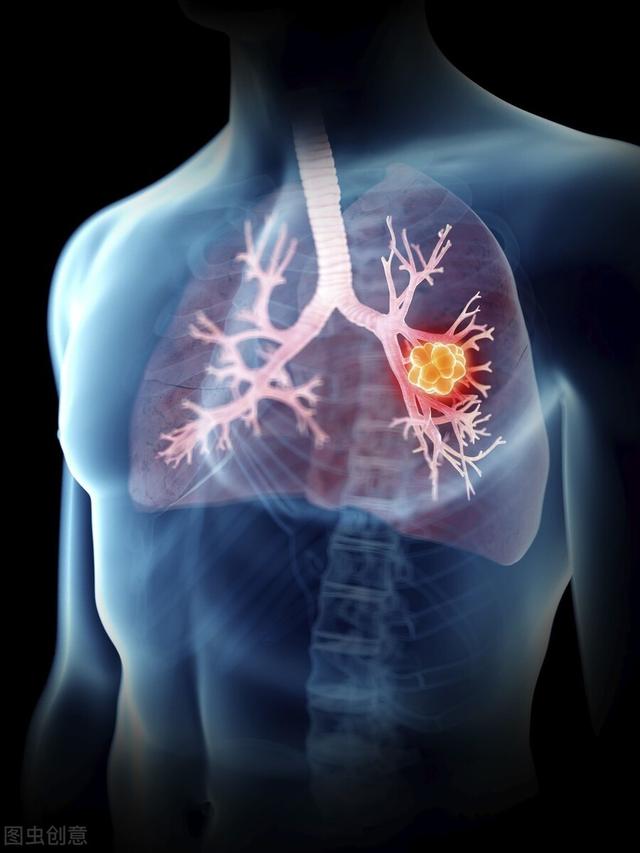

肺がんは現在、こう呼ばれている。ナンバーワン世界的にがん関連死で最も多い主要がんこの上なくその理由は。WHOが発表したデータによると、2012年だけでも、世界中で肺がんを発症した人の数は182.5万ドルこれは、全がん罹患者数と死亡者数の13.0%を占めている。1億5,900万ドル全がん死亡者の19.4%を占める!

これがいかに膨大な人口であるかは想像に難くない。したがって、肺がんの早期発見、早期診断、早期治療は非常に重要である。もちろん、肺がんが第1位というのは、罹患率も死亡率も第1位であることと密接な関係がありますが、同様に肺がんの症状が多く、非定型的なものが多いことも関係しています。では、肺がんが腰痛を引き起こす可能性はあるのでしょうか?もしそうだとしたら、肺がんによる腰痛と通常の腰痛の違いは何なのでしょうか?一般人である私たちは、それをどのように見分ければよいのでしょうか?今日はその話をしよう。

肺がんが背中の痛みを引き起こす可能性はあるのでしょうか?もしそうなら、何が原因なのでしょうか?

まずはその答えから:肺がんは背中の痛みを引き起こすことがある。.しかし、それは典型的なものではなく、一般的なものでもない。想像を絶する,つまらない結局のところ、私たちの肺がんは胸部で発生するのであって、これがどうして背中まで走るのか、ちょっと理解できない。

しかし実際は、肺がんの骨転移による腰痛なのだ。肺癌は多くの癌の中で最も骨転移を起こしやすい腫瘍の一つだからだ。そのため、痛みの原因がわからないときは、肺がんの骨転移を疑ってみるのもよいでしょう。ただ、他の要因による腰痛に比べれば、その可能性ははるかに低い。

もちろん、腰痛の原因となる肺がんの骨転移のほかに、腰痛を引き起こす可能性のある病気がもうひとつある。放射線痛私たちの狭心症と同じように、左肩や胸の後ろにも放散することがあります。私たちの狭心症のように、左肩や胸の後ろにも放散して背中の痛みを引き起こすことがあるように、この肺がんも胸や背中の痛みを引き起こすことがあります。これは主に、私たちのすべての神経が同じ神経根から放散し、神経伝導を通して背中の後ろまで放散し、胸や背中の痛みを引き起こすという事実と関係しています。

肺がんが背中の痛みを引き起こす主な理由は2つある:

ひとつは肺がんの骨転移で、背中の痛みは場所がまちまちで、どこにでも起こりうる;

もうひとつは、神経を伝わって放散痛を引き起こす痛みで、場所は比較的固定されており、主に胸の後ろ側である。